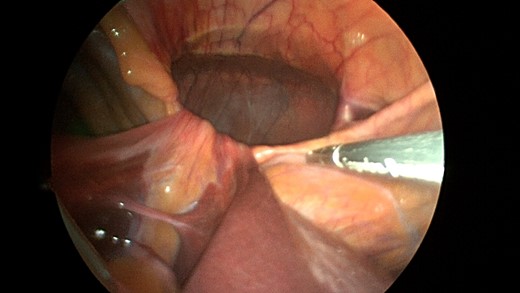

A sleeve of Parietex composite mesh cut to act as a suture bolster under the diaphragm edge to prevent the sutures from pulling through the diaphragm muscle.

CT scan is obtained for a specific diagnoses of Morgagni hernia in order to strategize your surgical approach. Minimally invasive laparoscopic techniques have become a popular option in the 21st century due to reduced intraoperative morbidity and quicker recovery rates [9]. Our case was unique in that the novel use of a sleeve of composite mesh was used as a bolster for the Ethibond suture as opposed to felt pledgets so the suture would not pull through the diaphragm. This sleeve of mesh was separate from the main mesh that was used to cover the overall repair (see pictures).